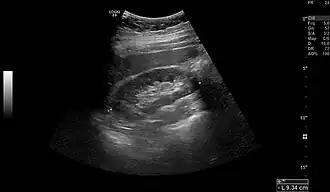

-

Normal adult right kidney as seen on abdominal ultrasound with a pole to pole measurement of 9.34 cm -

Imaging

Renal ultrasonography is essential in the diagnosis and management of kidney-related diseases.[49] Other modalities, such as CT and MRI, should always be considered as supplementary imaging modalities in the assessment of renal disease.[49]